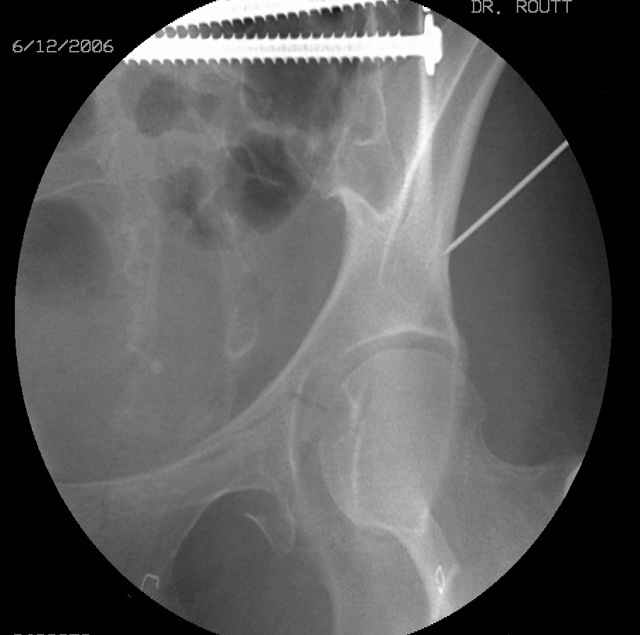

Here's a pic from the foot of the bed and you can see the clamp in the wound and the knee is extended so he must've had a tight rectus. The C-arm is rolled back to an obturator oblique image to reveal the anterior column...we put a slight outlet tilt to combine the images and give a better view of the anterior column...we can see the posterior column limb reduction in the wound, we can palpate the quadrilateral surface limb, and the image demonstrates the anterior column portion...you can adjust the tilt and rotation to image tangentially to the fracture plane if you'd like. We've inserted a 2mm K wire to site the starting point and aim/orientation for the drill and screw

Prone Imaging

same image, just another look.